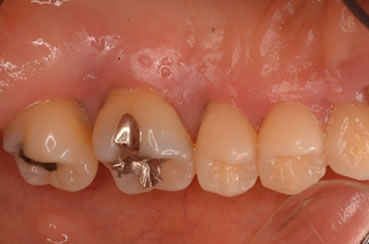

症例3

治療の特徴(患者I様)

初診 2015年5月1日 / 経過 2018年7月2日

| 治療期間 | 2年5カ月(2019年5月時点SPT中) |

|---|---|

| 費用 | 保険内治療 |

| 歯間外科処置 | 1ブロック約9,000円(3割負担) |

| 治療のデメリット | 外科処置を伴う・治療期間が長い(歯槽骨の安定を見る為) 歯周 外科処置後歯肉の位置が下がる為知覚過敏が起こりやすい |